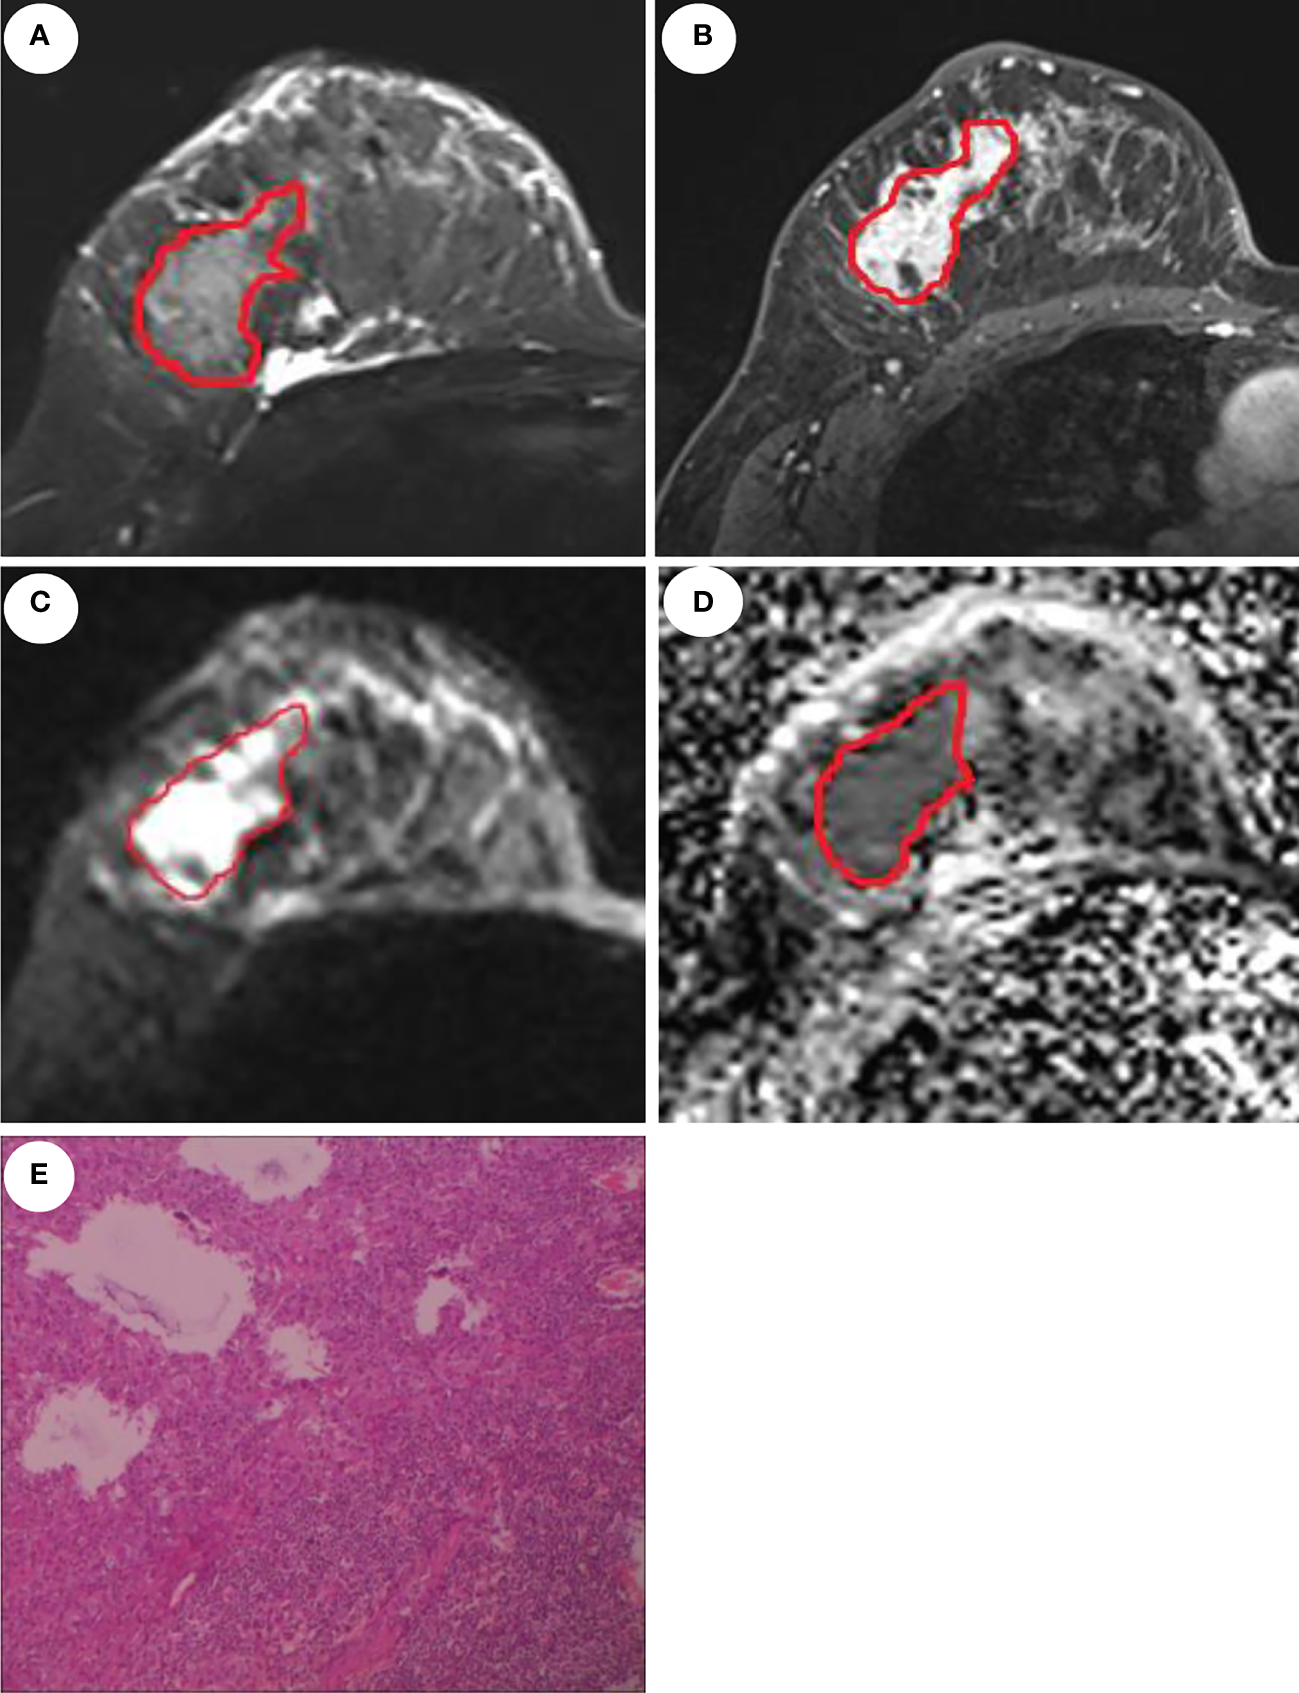

ROI delineation rules were as follows: first, on the DCE images, the phase I image with the highest intensity was selected and an ROI was contoured along the margin of the tumor. Second, on the T2WI image, the primary tumor was defined by contouring the margin of the tumor which had a slightly higher signal. Third, the ROI on the DWI images was draw to cover the entire high-signal-intensity area. Finally, the ROI on DWI images was then transferred to ADC maps. The ROI excluded any visible liquefaction, necrosis, and cystic regions. Figure 2 shows the ROI delineation and pathological image of a case with presence of LVI.

Figure 2

MRI and pathological images of a 46-year-old patient with invasive ductal carcinoma and LVI. Manual delineation of the region of interest on the T2WI (A), DCE (B), DWI (C), and ADC (D), respectively. (E) displays the presence of LVI.